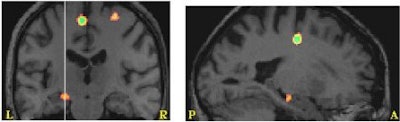

Accuracy was measured in the first task, and reaction times in the second. The analysis showed that normalized cerebral blood flow (CBF) to the hippocampus complex correlated positively with better performance on both tasks. "The more accurate they were, the greater the blood flow," Whatmough said.

Reaction times on a word-meaning judgment task decreased with increased regional cerebral blood flow to the right parahippocampal gyrus (below) and the left hippocampus (above). Images courtesy of Christine Whatmough, Ph.D.

In addition to correlating with the accuracy of responses, the regional CBF showed clear lateralization -- right for picture-naming and left for word-meaning judgments, according to neurologist Dr. Howard Chertkow, another member of the research team.